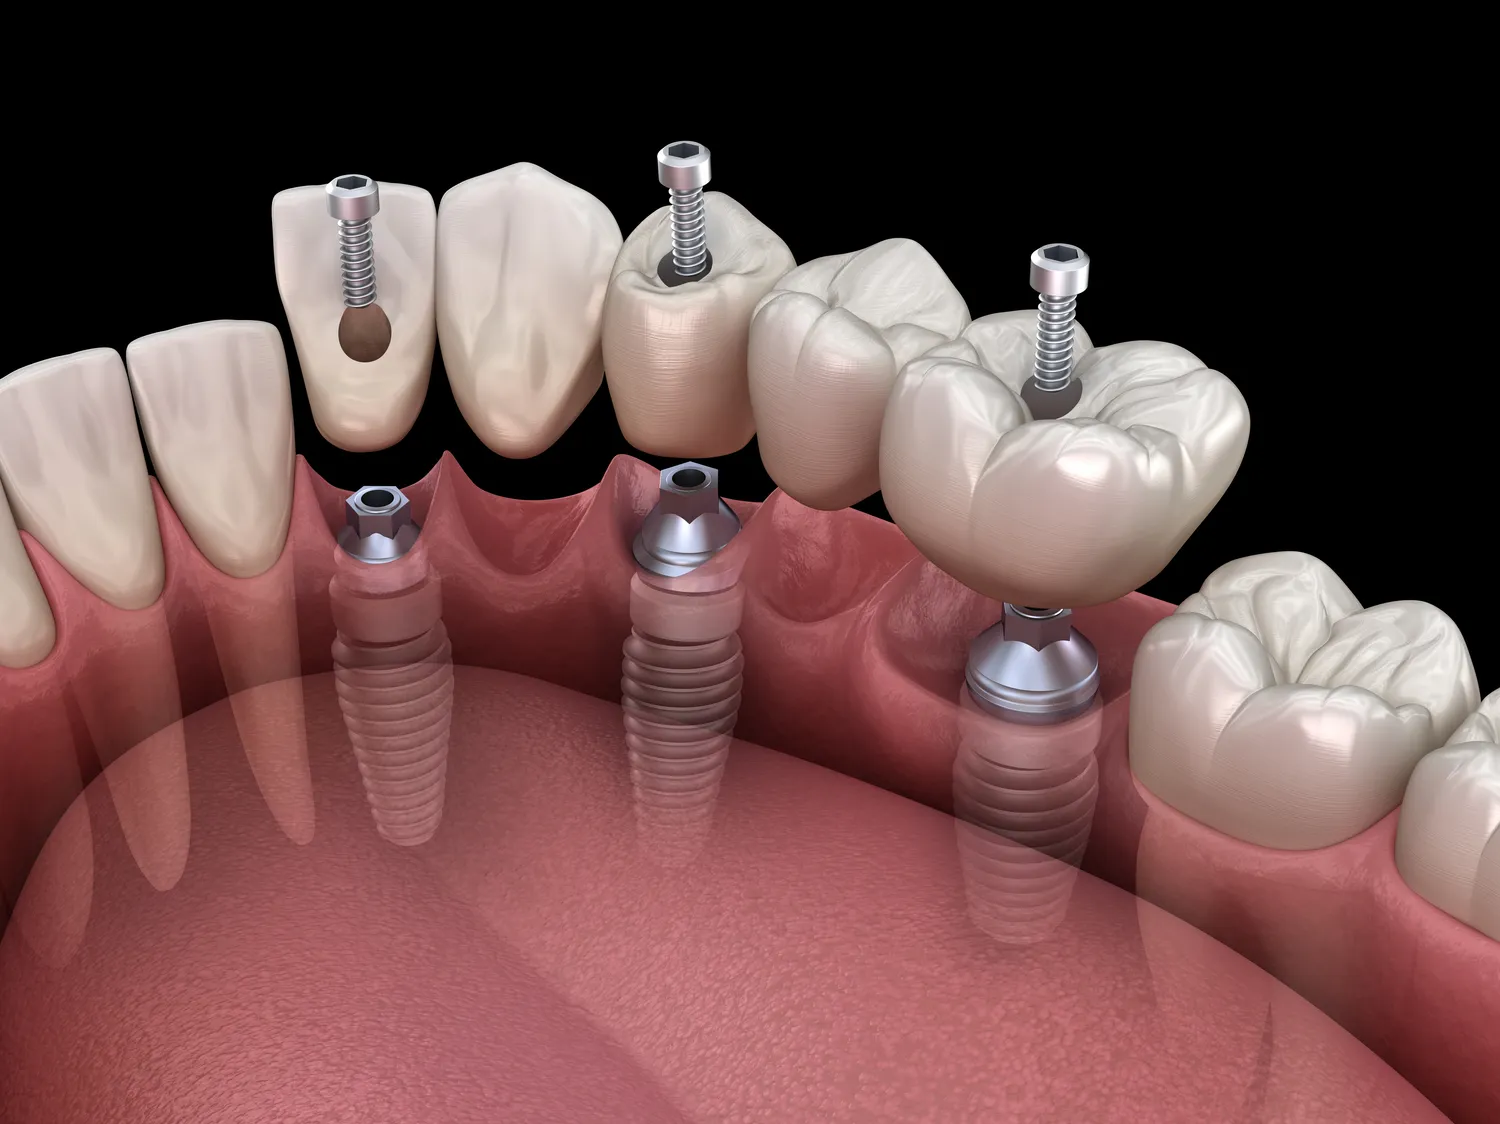

Proces zakupu implantów w jeden dzień w Gryficach zaczyna się od konsultacji stomatologicznej, podczas której lekarz ocenia stan uzębienia pacjenta oraz przeprowadza niezbędne badania diagnostyczne. Na podstawie wyników tych badań lekarz podejmuje decyzję o możliwości wykonania zabiegu w trybie ekspresowym. Kluczowym elementem jest również omówienie oczekiwań pacjenta oraz przedstawienie mu dostępnych opcji leczenia. Po zaakceptowaniu planu leczenia następuje etap przygotowań do zabiegu, który może obejmować wykonanie zdjęć rentgenowskich oraz tomografii komputerowej. W dniu zabiegu pacjent otrzymuje znieczulenie miejscowe, a następnie lekarz przystępuje do wszczepienia implantu. Cały proces jest zazwyczaj bardzo szybki i trwa kilka godzin. Po wszczepieniu implantu lekarz montuje tymczasową koronę, co pozwala pacjentowi na normalne funkcjonowanie i estetyczny wygląd od razu po zabiegu.

Rehabilitacja po wszczepieniu implantów w jeden dzień w Gryficach to kluczowy etap procesu leczenia, który ma na celu zapewnienie prawidłowego gojenia się tkanek oraz integracji implantu z kością. Czas trwania rehabilitacji może być różny w zależności od indywidualnych predyspozycji pacjenta oraz specyfiki przeprowadzonego zabiegu. Zazwyczaj pierwsze kilka dni po wszczepieniu implantu to okres intensywnego gojenia się tkanek miękkich oraz adaptacji organizmu do nowego elementu. W tym czasie zaleca się unikanie twardych pokarmów oraz dbanie o higienę jamy ustnej zgodnie z zaleceniami lekarza. Po około tygodniu następuje pierwsza kontrola stomatologiczna, podczas której lekarz ocenia postęp gojenia i podejmuje decyzję o dalszych krokach. W ciągu kilku miesięcy następuje proces osteointegracji, czyli zespolenia implantu z kością szczęki lub żuchwy. To kluczowy moment dla trwałości implantu i jego funkcjonalności na długie lata. Regularne wizyty kontrolne pozwalają na monitorowanie postępów rehabilitacji oraz ewentualne dostosowanie zaleceń dotyczących diety czy pielęgnacji jamy ustnej.